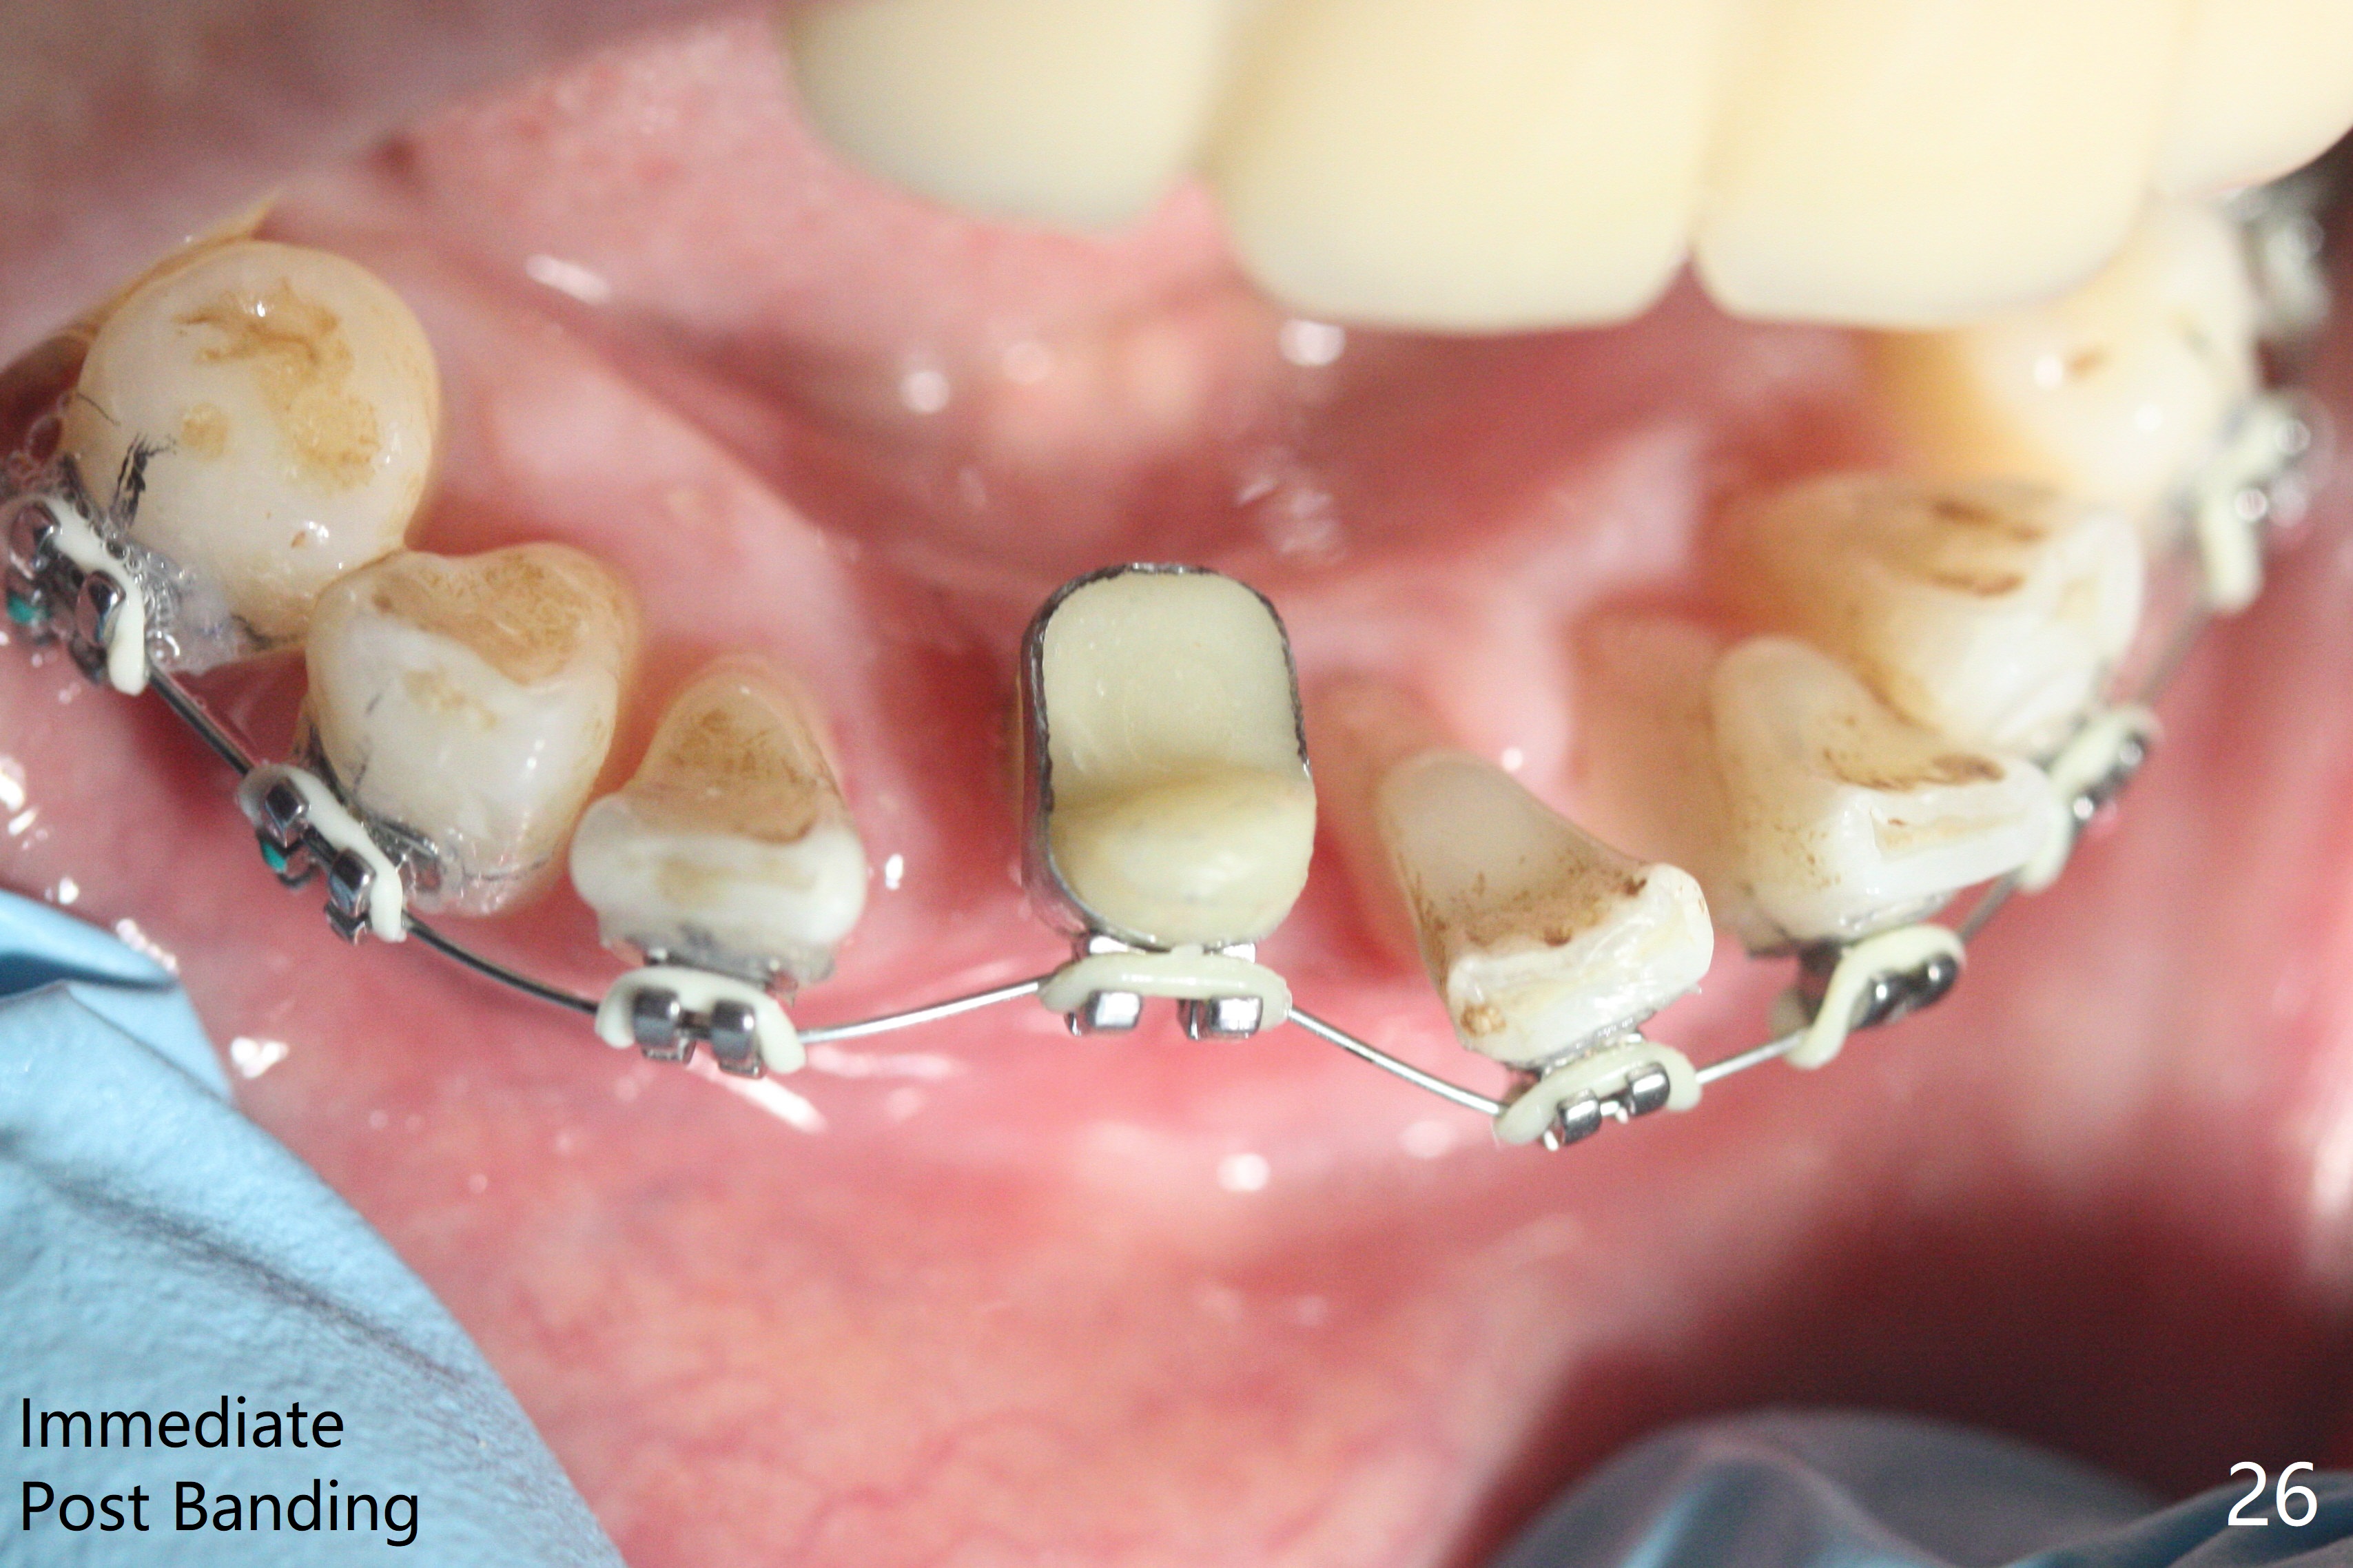

56岁女十分恐惧治疗,缺失右下1,其余切牙由于骨质吸收颊侧移位(图一:1,2),但是她不愿意拔除,同意右下1种植,牙周骨手术,植骨;植体整合后作为支抗,矫正移位下门牙。为了防止忘记舌侧瓣分离,先做舌侧切口(图二),然后颊侧瓣松弛分离(图三),包括使用前牙隧道刀(图四)切断颊侧骨膜,松弛到颊侧瓣能向舌侧牵拉3-4毫米(图五),舌侧瓣骨膜下广泛,深部分离(好像不能切断骨膜,图六),放置导板,磨平狭窄的牙槽嵴(图七:O(osteotomy)),植入2.5x12(4)毫米一段式植体(图八:故意舌侧植入,以便以后矫正),在颊侧骨板打多个出血洞(图八:箭头),然后把在平的器皿上形成的粘性骨板(sticky bone,图九),放置于植体和移位切牙周围(图十),接着使用消毒过的橡皮障punch(图十一(纸头相当于PRF膜;事先给助手示范))在三个PRF膜(图十二)打洞,套在植体和门牙上(图十三: 箭头),防止膜(图十四)和骨块(图十五,十六:*)移位,最后还必须使用最原始方法牙周敷料保护伤口(图十七)。术后9天,舌侧牙周敷料脱落,伤口稍微裂开(图十八)。术后18天撤除敷料,伤口裂开处有新鲜肉芽组织生长(图十九(*:下面是填入的骨粉,将是增宽的牙槽嵴(如果你是乐观主义者)),二十)。病人十分感激我们帮助她度过难关。她的确有sleep apnea,否定tongue thrust。术后三个月植体周围没有明显骨质吸收(图二十一至二十三),左下1,2轻度反合(图二十四),植体周围软组织健康(图二十五),5-5安置矫正器(图二十六,二十七,12 niti)。一周后下切牙向舌侧移动(图二十八),左下1,2反合纠正(图二十九)。再一周变化不大(图三十),植牙圈有些松动,两周后将重做临时牙冠,槽往舌侧移动。结果病人提前回来,植牙槽舌侧移位。一周后右下2不适(图三十一),尝试近中牵引(图三十二)。